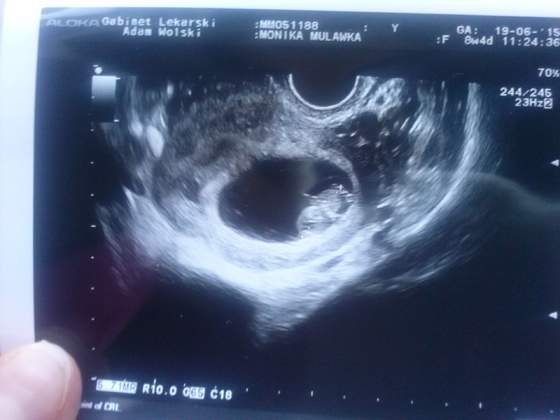

a to mój groszek,usg z 19.06